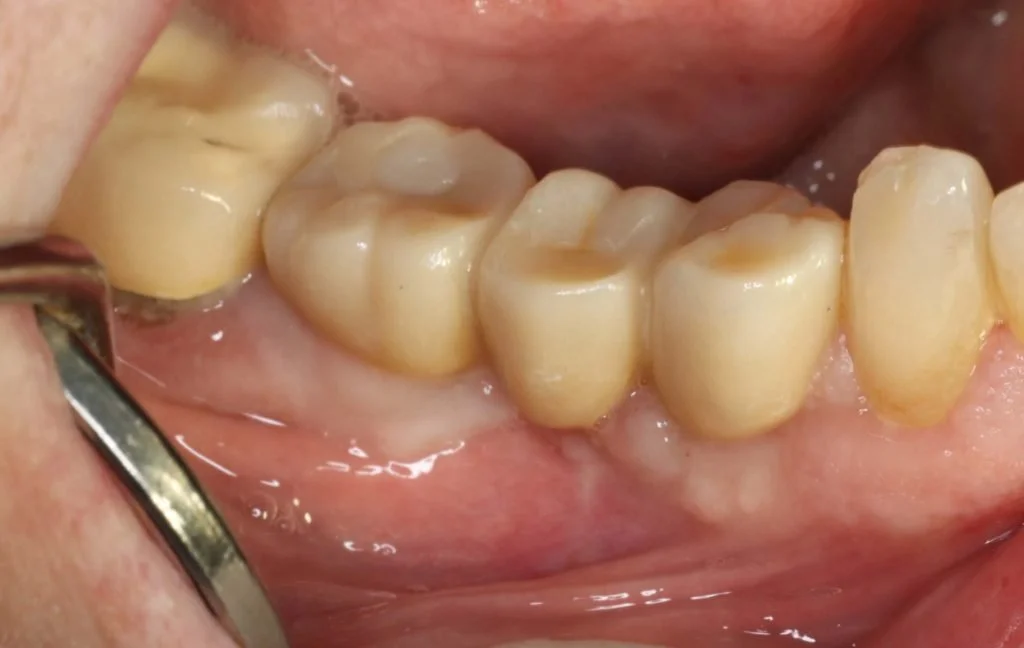

Open tray screw retained impression copings were then attached and confirmed with radiographs, and a three-unit veneered zirconia bridge was constructed using Variobase lab cemented abutments to provide an all-in-one screw-retained restoration.

The definitive restoration was then inserted and checked for passivity of fit. The abutment screws were then definitively torqued to 35 Ncm. The access cavities were restored with PTFE tape and composite resin.